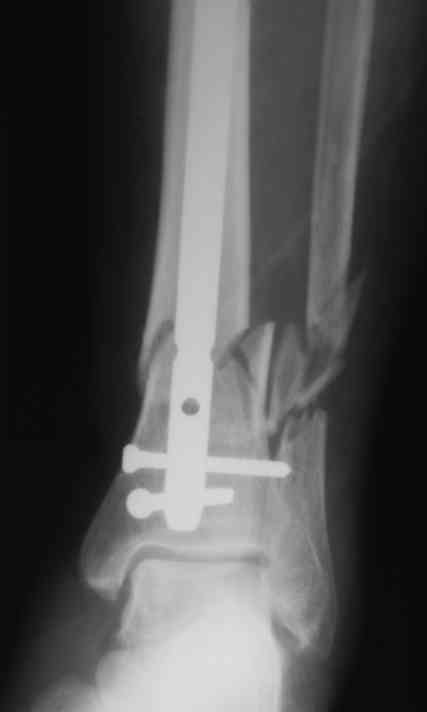

Уважаемые коллеги!БИОС занимаемся недавно. Хотелось бы услышать Ваше мнение па данному клиническому примеру. Пациенту 74 года.

Выполнен открытый БИОС, обнаружен выраженный остеопороз, один из проксимальных винтов(самый верхний) и один из дистальных (нижний) "сорвались". В средней трети - косо-поперечный перелом (на фото не захвачен) с хорошей репозицией. Клинически фиксация переломов стабильна. Выполнить МОС малоберцовой кости не представлялось возможным из-за фликтен по латеральной поверхности голени.

4. Диаметр стержня - 11, нержавейка, производитель Санатметалл